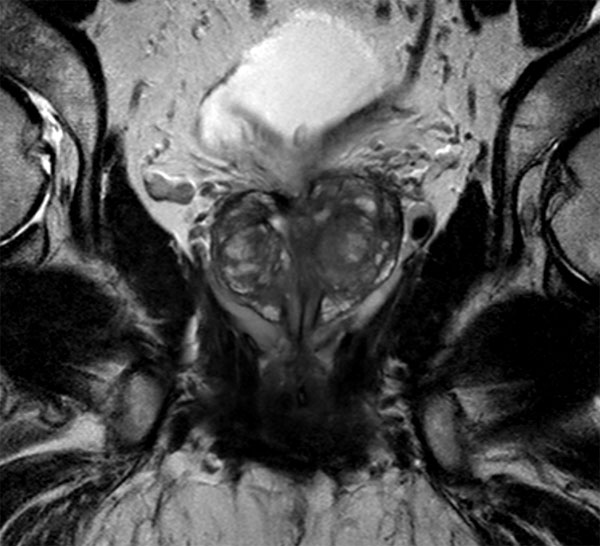

75-year old male. dS Endo coil used to visualize tumor in peripheral gland.

Coronal T2w TSE